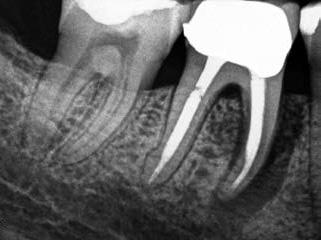

Egy 38 éves nőbeteg a korábban kezelt jobb felső második kisőrlőfogából (1.5) kiinduló mérsékelt fájdalom miatt jelentkezett rendelésünkön. A kórtörténetében jelen panasza szempontjából releváns információ nem szerepelt. A beteg a klinikai vizsgálat során vertikális kopogtatásra enyhe érzékenységet jelzett. A kérdéses fog körül mérhető szondázási mélység és a fogmobilitás fiziológiás volt. Periapicalis röntgenfelvételen egy, a fog gyökércsúcsán túl presszálódott betört gyökérkezelő műszerből származó eszközfragmentumot láttunk (2. a. ábra). A preoperatív CBCT-felvétel a buccalis csontlemez épségét igazolta (2. b-c. ábra). A fog revíziója öt hónappal korábban történt. A már előzőleg gyökérkezelt, gyökértömött, majd revideált 1.5-ös fog esetében a diagnózisunk periodontitis periapicalis symptomatica volt. A periapikális elváltozás kezelése érdekében navigált endodonciai mikrosebészeti beavatkozást végeztünk.

a-m. ábrák: Preoperatív röntgenfelvétel (a) és preoperatív CBCT-felvétel a jobb felső 5-ös (1.5) fogról, sagittalis (b) és axialis (c) nézetek. Az intraorális szkennelés során kapott STL-fájl (d). A 1.5-ös fog navigált endodonciai mikrosebészeti beavatkozásához tervezett sablon (e). A 1.5-ös fog navigált endodonciai mikrosebészeti beavatkozásához nyomtatott sablon (f). Teljes vastagságú mucoperiostealis lebenyt emeltünk (g). A sablont a helyére illesztettük, és a csontablak határait jelöltük (h). A fog gyökerén kívül eső, betört eszköz a 1.5-ös fog periapicalis régiójában (i). Az eltávolított betört eszköz (j). A rezekció, retrográd preparáció és a TotalFill BC RRM Fast Set Putty anyaggal elkészített retrográd gyökértömés utáni röntgenfelvétel (k). A lebenyt varratokkal rögzítettük (l). A kétéves kontroll során készített röntgenfelvétel (m).

gítségével tovább módosítottuk. Az így kapott sebészi sablon egyértelműen meghatározta a periapikális terület eléréséhez szükséges csontablak határait (2. e-f. ábra) Helyi érzéstelenítést követően teljes vastagságú mucoperiostealis lebenyt képeztünk, majd a buccalis csont feltárását követően (2. g. ábra) a sablon segítségével bejelöltük a preparálandó csontablak határait (2. h. ábra). A csontablak kialakítása során Piezotome CUBE LED kézi-darabot alkalmaztunk, majd a leemelését követően a betört eszközt megkerestük (2. i. ábra) és eltávolítottuk (2. j. ábra). A rezekciót ultrahangos megmunkáló fejekkel (ACTEON) végeztük, majd retrográd preparáció következett.

A retrográd gyökértömés elkészítése során TotalFill BC RRM Fast Set Putty-t (FKG) használtunk (2. k. ábra). A lebeny széleit 5/0-s Prolene varratokkal egyesítettük (2. l. ábra). A varratok a műtétet követően 72 órával kerültek eltávolításra. A beteg két évvel később kontrollröntgen készítése céljából érkezett rendelőnkbe. A vizsgálat során a fog tünetmentesnek és funkcióképesnek bizonyult (2. m. ábra).